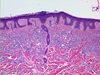

What is Parakeratosis?

What is hyperkeratosis?

Pathology?

Pathology?

What is Ancanthosis?

Pathology?

Pathology?